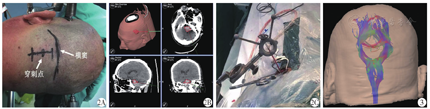

男性,50岁,主因"突发意识不清6 h"于2017年6月29日收治于解放军总医院第七医学中心神经外科。既往有高血压病史10年,未规律监测血压及服药控制。体检:血压200/100 mmHg(1 mmHg=0.133 kPa),神志深昏迷,GCS评分5分,双侧瞳孔圆形,直径约2 mm,对光反射迟钝,四肢肌力Ⅱ级,双侧巴氏征阳性。辅助检查:头颅CT示桥脑出血,出血量约8 mL(图1A~B)。初步诊断:脑干出血;高血压病3级,极高危组。入院后予以降压、止血等治疗,发病后15 h行无框架导航系统辅助下脑干血肿穿刺置管引流术。全身麻醉下,先仰卧位行气管切开术,然后右侧卧位,注册导航,穿刺点位于左侧横窦下2 cm,乙状窦和中线之间(图2A),根据导航指示设计穿刺路径(图2B~C)。术中切开头皮、皮下及肌肉层,颅骨钻孔,切开硬膜,调整无框架导航臂,置入带枕芯引流管,深度距小脑皮层约6 cm,拔出针芯,转动引流管同时以5 mL注射器缓慢轻抽出血肿约5 mL,缝合肌肉、皮下及头皮,固定引流管,术毕。术后2 d复查头颅CT提示引流管位置良好,血肿清除满意(图1C~D);头颅核磁DTI重建显示主要的神经纤维束得以保留(图3),拔除引流管。术后5 d患者清醒,恢复过程顺利,并发肺部感染,经抗感染治疗后好转,无消化道出血、中枢性高热等并发症,住院时间23 d,出院后行康复治疗。随访5个月,GOS评分4分。

2A:体位及头皮切口;2B:术中导航显示血肿位置及穿刺路径;2C:置管成功,可见引流管内血肿(混有脑脊液)